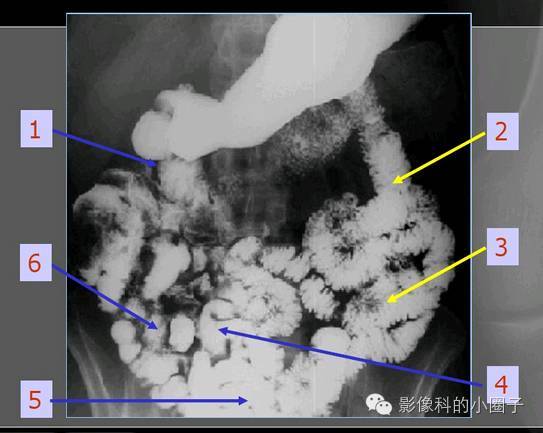

小肠造影正常x线表现

小肠x线下分区分组

小肠影像解剖及分组